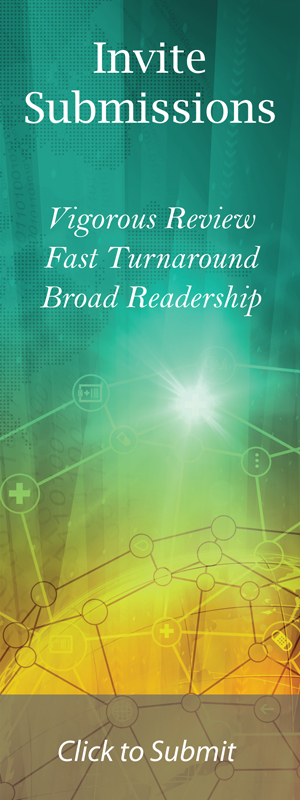

A review of imaging studies of the lumbar spine with and without contrast showed a variable enhancing lesion with what appears to be some fluid levels in a multilobulated lesion of the left L4 neural foramen that was read by the radiologist as a hemangioma or possible nerve sheath tumor (Fig. 1). She has had imaging studies as recently as 3 years ago which she reported did not show any abnormality in the lumbar spine.

Click for large image | Figure 1. Preoperative T1 sagittal (right) and axial (left) MRI with contrast showed a variable enhancing lesion with possible fluid levels in a multilobulated lesion of the left L4 neural foramen. |

Postoperatively, the patient reported that she had pain at the incision and intermittent radiation to her left gluteal area, however, she denied any radiation to her left lower extremity. The patient had an uneventful recovery and was discharged home on the 3rd postoperative day. The postoperative MR image revealed resection of the nerve root sheath mass (Fig. 2). She continues to be asymptomatic on follow-up at 18 months.

Click for large image | Figure 2. Postoperative T1 sagittal (right) and axial (left) MRI with contrast demonstrating resection of the nerve root sheath tumor. |